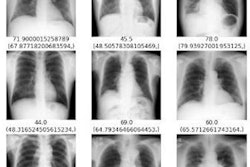

Grad-CAM visualizations for estimates from InceptionResNetV2 for estimating sex from hand x-rays. Image courtesy of Forensic Science International: Reports through CC BY 4.0.To that end, the group for the first time aimed to employ a CNN for sex estimation from Thai hand x-rays. They used images from 385 men and 788 women and split them into training, validation, and test sets. Among seven CNN models evaluated on 100 unseen male and female x-rays each, a model that employed InceptionResNetV2 architecture demonstrated superior performance. The model achieved an accuracy of 87% and an F1-Score (precision and recall) of 87%.

In addition, the group sought to understand the strategy behind the CNN's estimates by applying a Grad-CAM visualization technique. The visualization results indicated that the model correctly identified x-rays of male hands by focusing on the second to fifth metacarpal bone (typically larger and longer in men) and the second to fifth proximal phalanges. When estimating radiographs of female hands, the model primarily emphasized the second metacarpal bone.